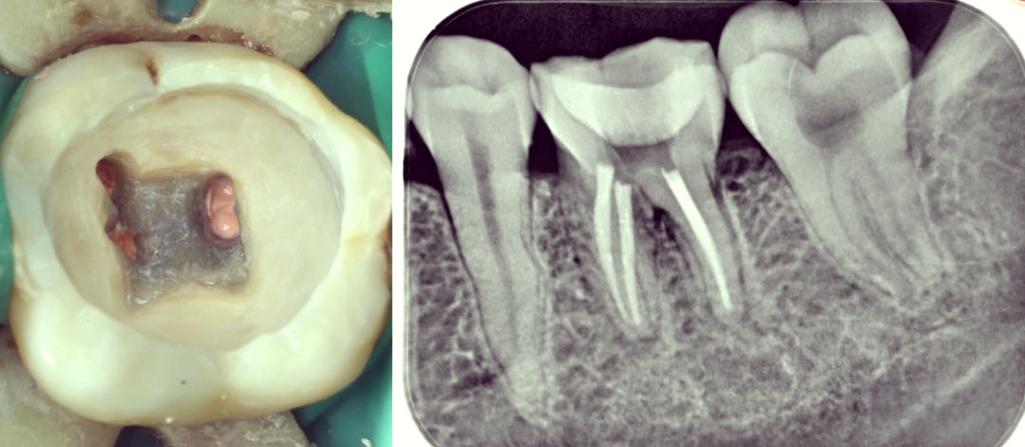

(图片来源网络,侵删)- 确认桩核的形态、高度、位置、表面粗糙度、与牙体组织的密合度均符合要求。

(图片来源网络,侵删)- 将混合好的硅橡胶轻柔地放入托盘内。

- 重点检查:桩核形态是否清晰完整?边缘线是否清晰连续?龈沟形态是否清晰?有无气泡或缺损?如有问题,需重新取模。

- 影像学评估: 术前必须拍摄根尖片,了解桩核的长度、直径、形态、与根管壁的密合度、根管弯曲度、根尖情况、有无根折等。